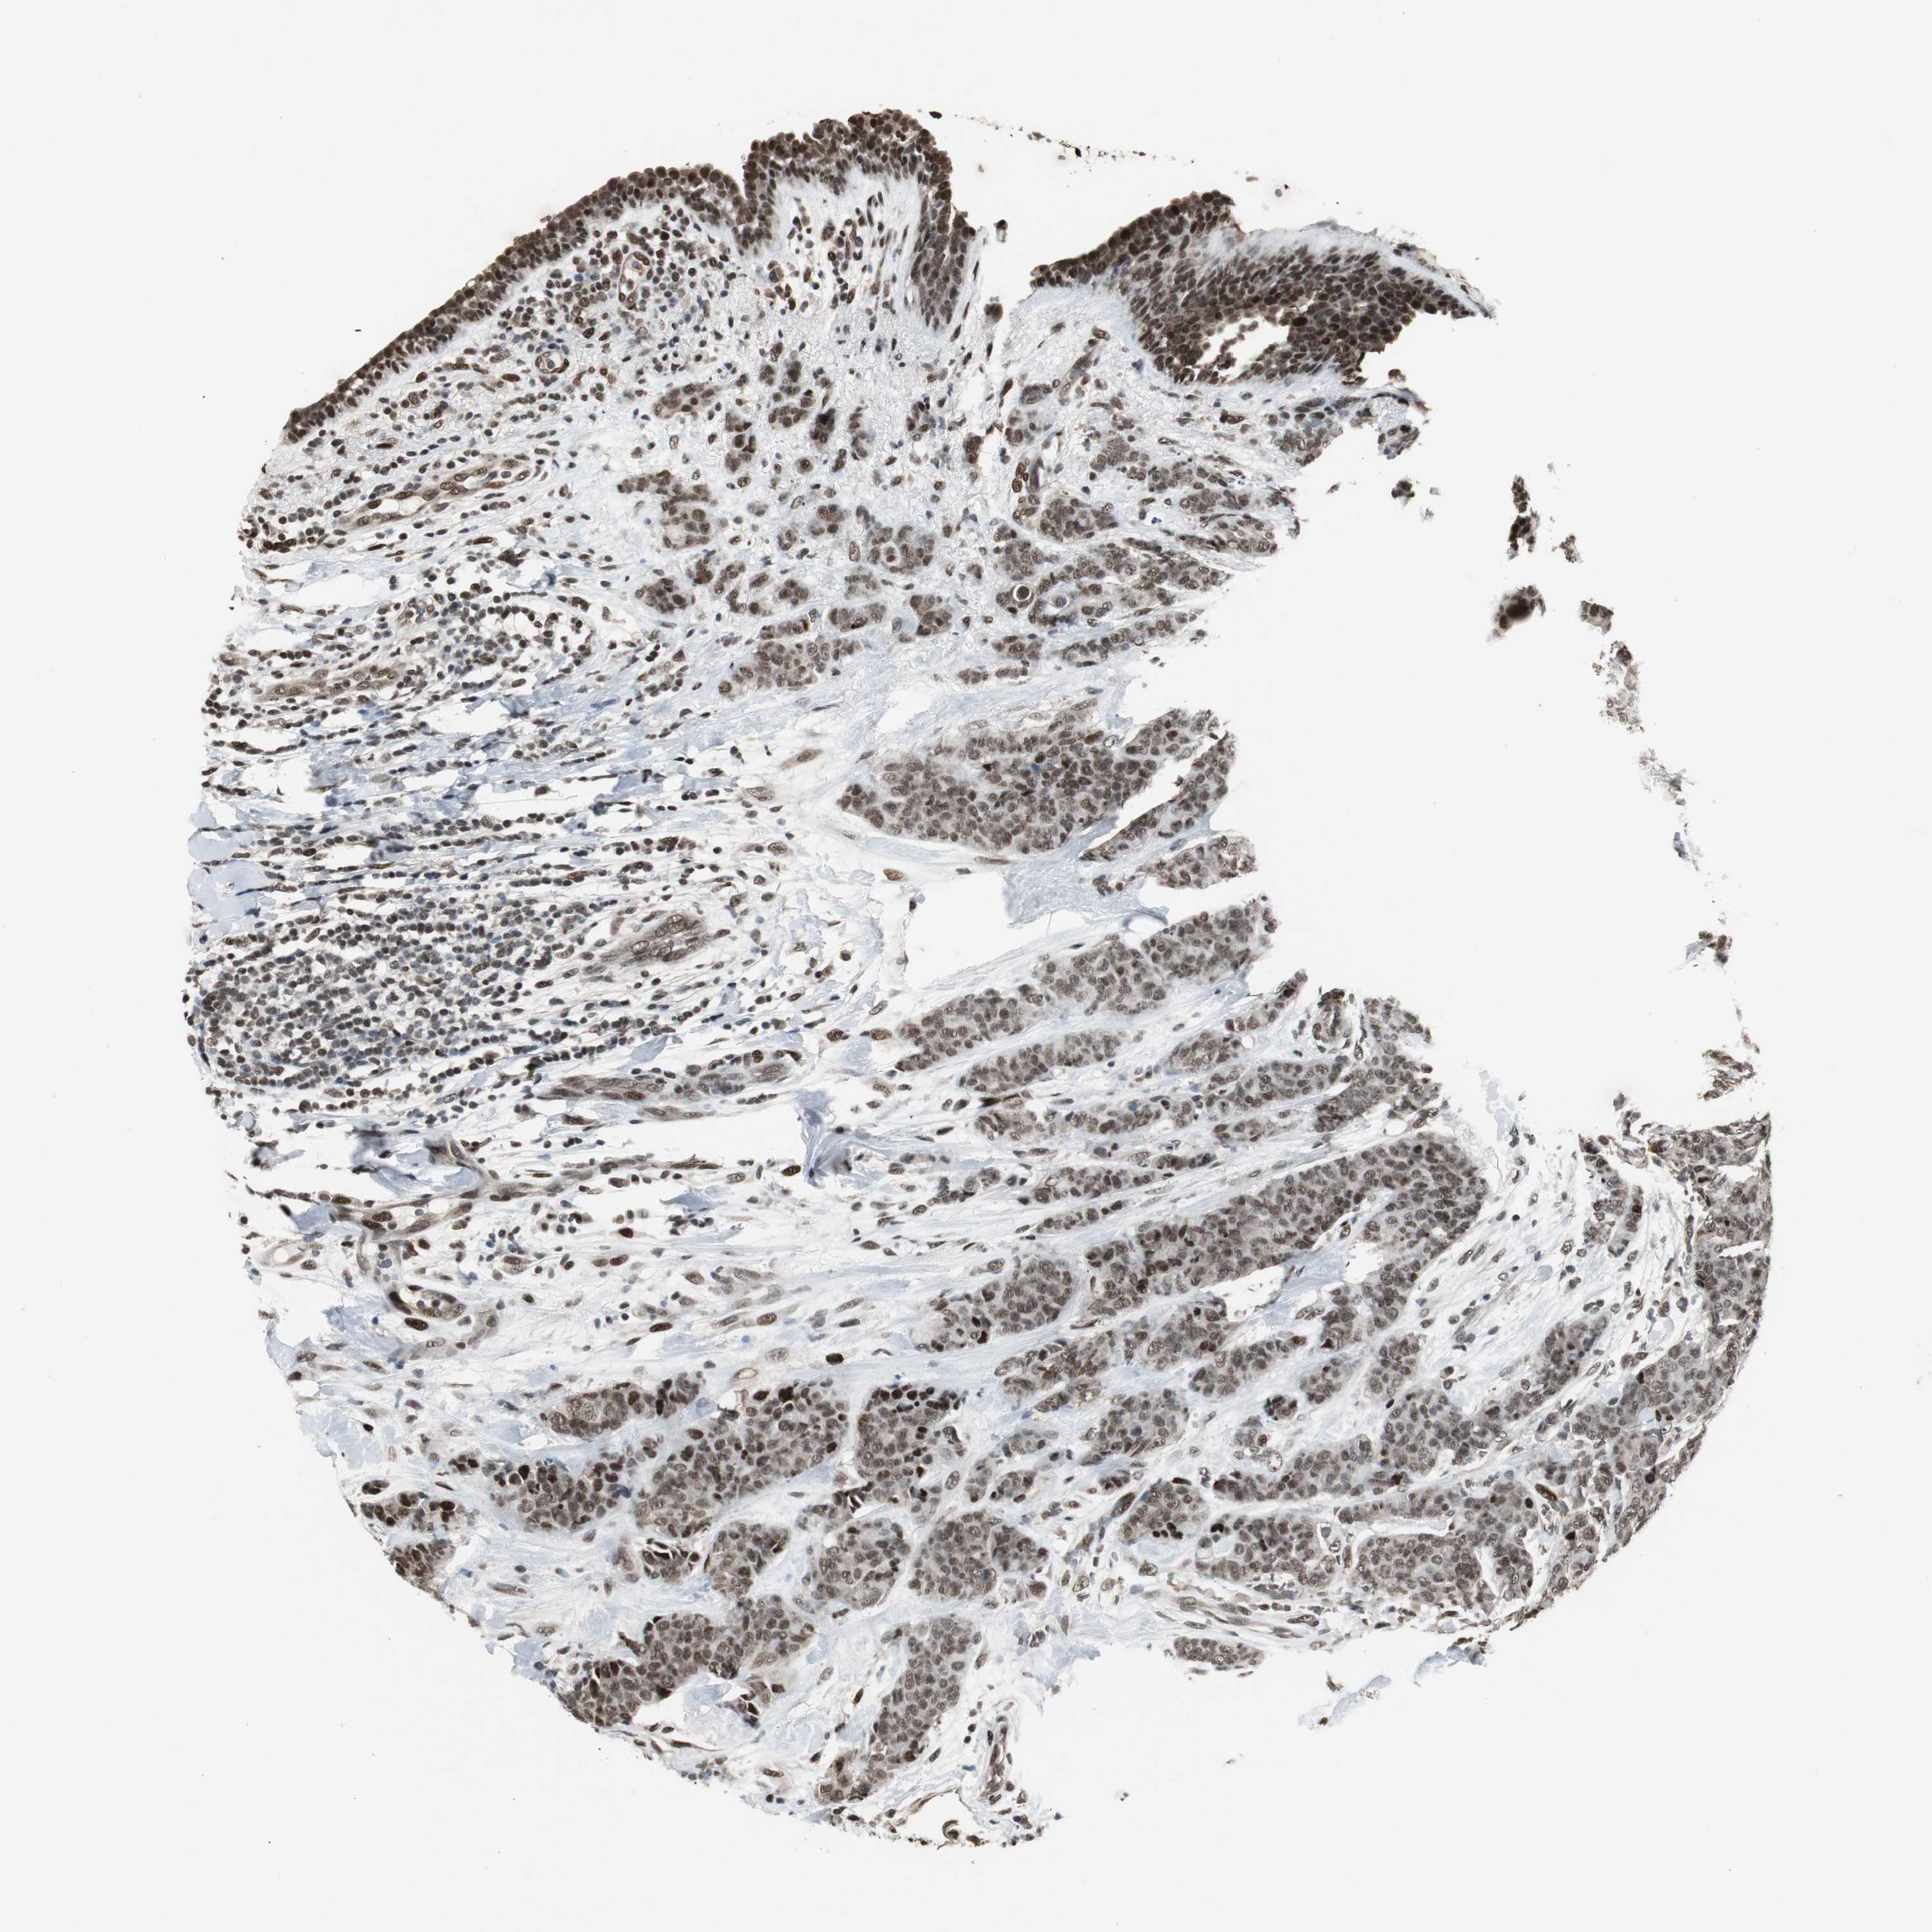

CANCER BREAST CANCER Show tissue menu

BRCA TCGA BRCA VALIDATION PROTEIN EXPRESSION